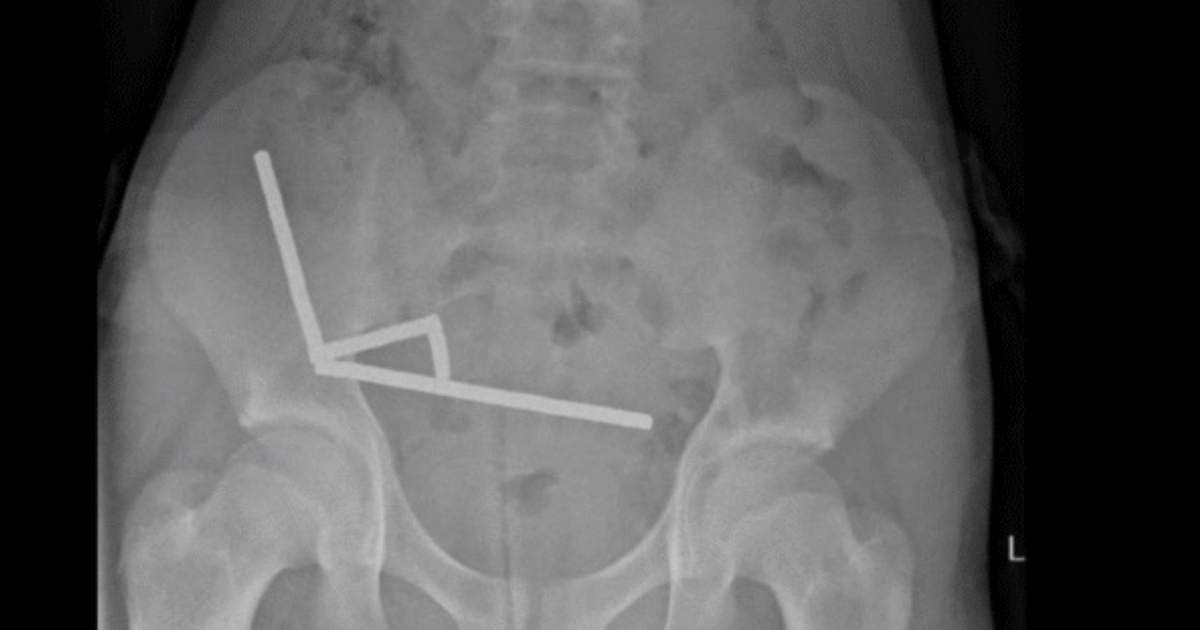

Tinejdžer s Novog Zelanda progutao 200 magneta, kirurzi mu uklonili dio crijeva

TRINAESTOGODIŠNJAK s Novog Zelanda morao je na hitnu operaciju uklanjanja dijela crijeva nakon što je progutao gotovo 200 snažnih magneta kupljenih online, unatoč zabrani njihove prodaje.